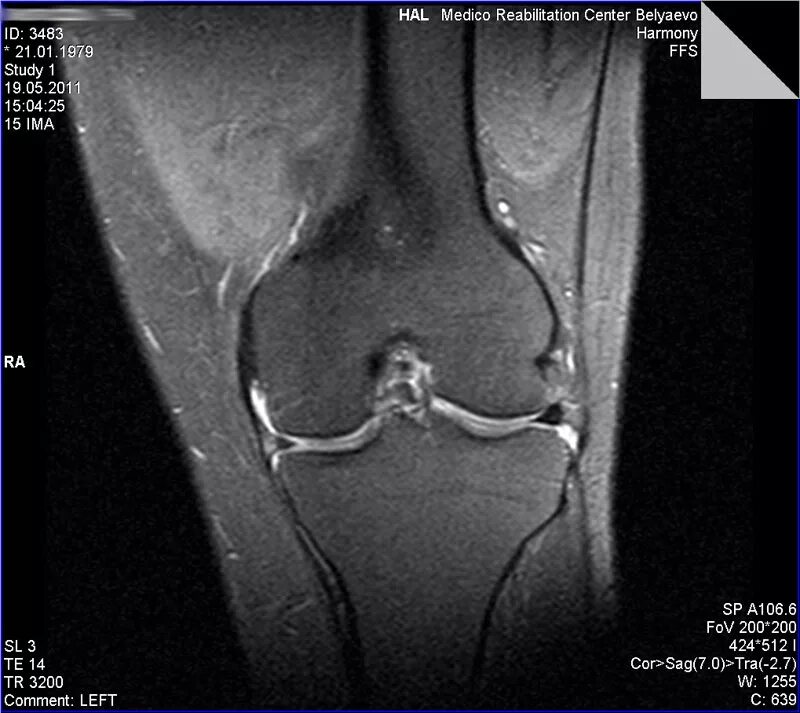

Повреждение мениска мрт